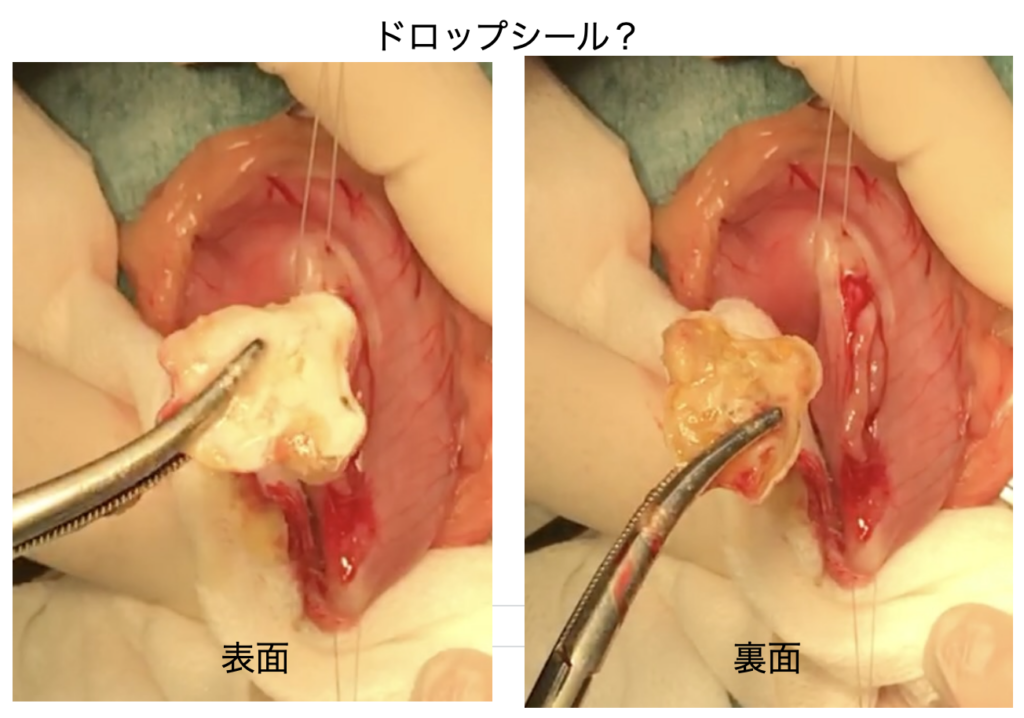

胃内に1辺が2cmほどの石(観賞魚の水槽で水草をくくりつける石?)人工的な石で針金が飛び出ていました。胃内に異物もあったのでそれも取り出しました(最近流行りの立体シール『ドロップシール』が出てきました)。テレビで見てドロップシールの存在は知っていたのですが手術で摘出した際にはプラスチック片だと思いました。ドロップシールは小学校低学年くらいの児童で人気の立体シール(ぷっくりシール)で、透明樹脂で飴玉のように盛り上がった、つやつやした質感が特徴のデコレーションアイテム。文房具店等では売り切れ続出の人気とのこと・・消化管から出てきた立体シールの絵柄などは確認できませんでしたが、当院スタッフによるとドロップシールだろうとのこと。